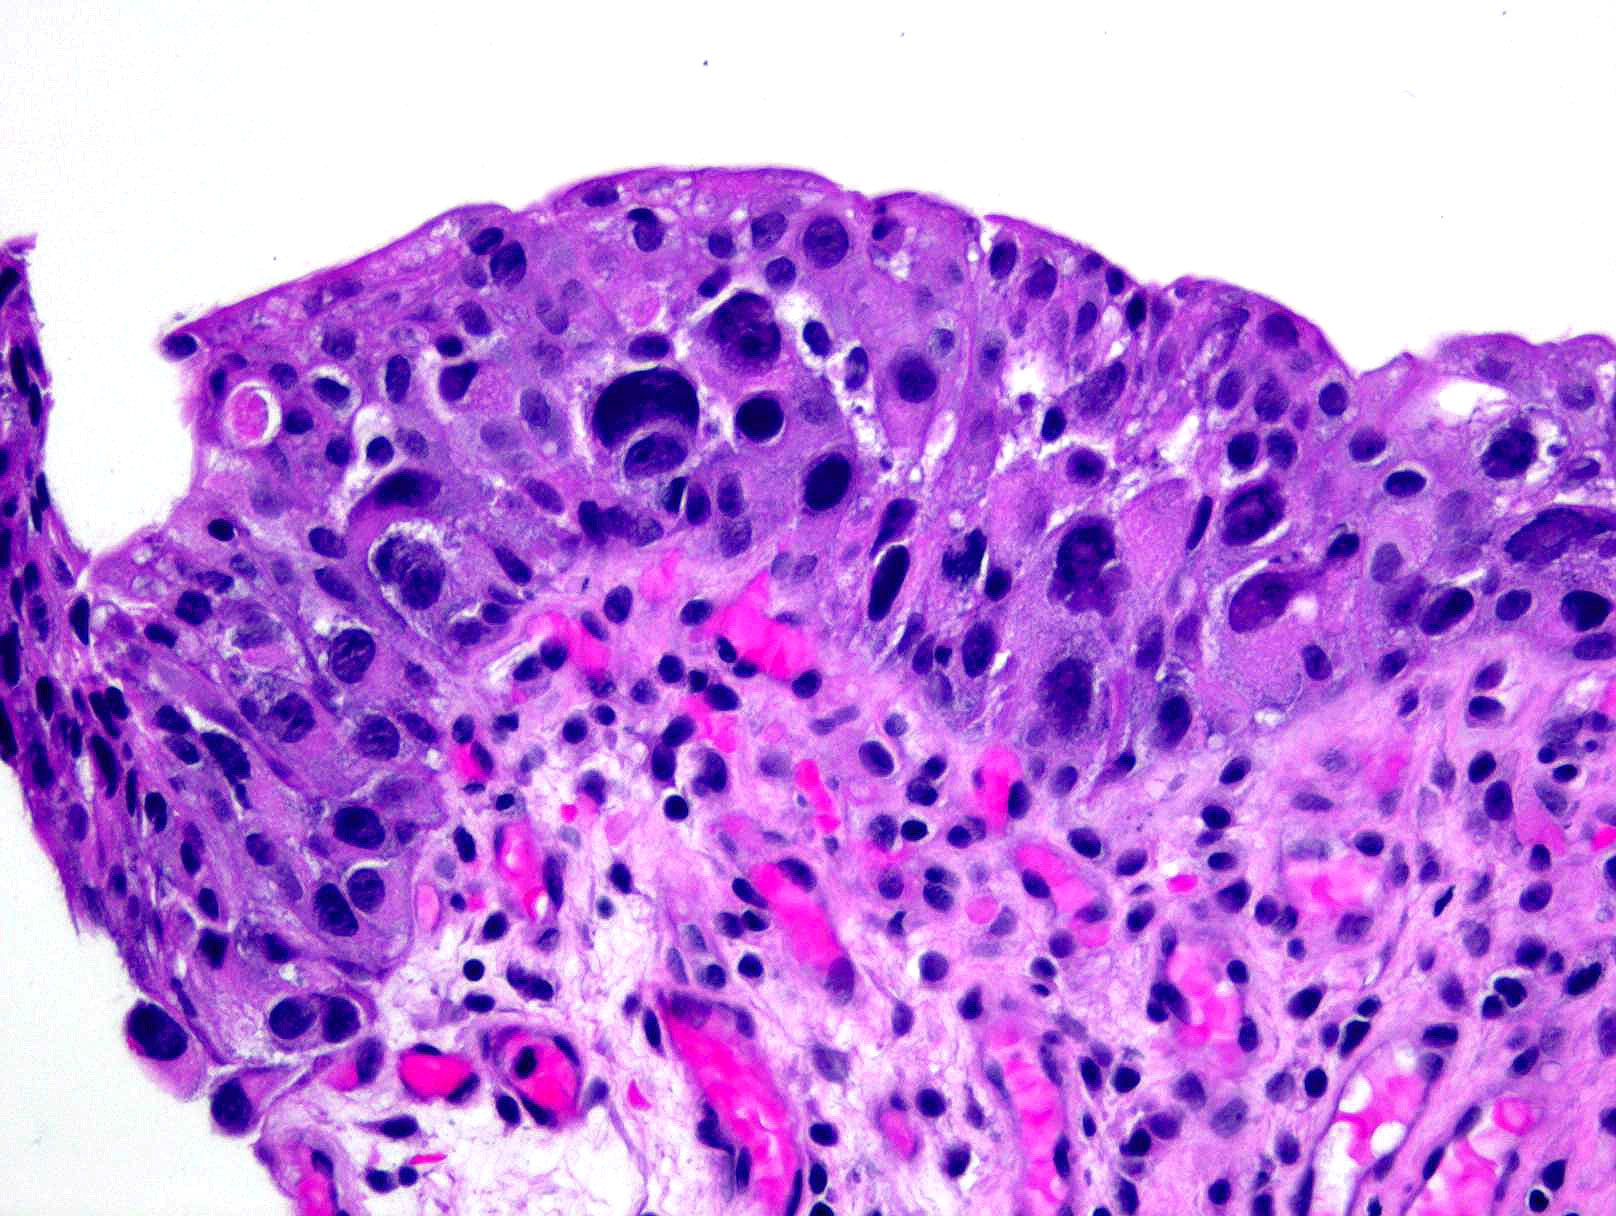

Consensus grade: Carcinoma in situ (CIS)

Show diagnosis by expert panel members| User | Diagnosis | Difficulty | Comment |

|---|---|---|---|

| Pathologist 1 | Carcinoma in situ (CIS) | Typical | |

| Pathologist 2 | Carcinoma in situ (CIS) | Typical | |

| Pathologist 3 | Carcinoma in situ (CIS) | Borderline higher | |

| Pathologist 4 | Carcinoma in situ (CIS) | Typical | |

| Pathologist 5 | Carcinoma in situ (CIS) | Typical | |

| Pathologist 6 | Carcinoma in situ (CIS) | Typical | |

| Pathologist 7 | Carcinoma in situ (CIS) | Typical | |

| Pathologist 8 | Carcinoma in situ (CIS) | Typical | |

| Pathologist 9 | Carcinoma in situ (CIS) | Typical | |

| Pathologist 10 | Carcinoma in situ (CIS) | Typical | |

| Pathologist 11 | Carcinoma in situ (CIS) | Typical | |

| Pathologist 12 | Carcinoma in situ (CIS) | Borderline lower | |

| Pathologist 13 | Carcinoma in situ (CIS) | Typical | |

| Pathologist 14 | Carcinoma in situ (CIS) | Typical | |

| Pathologist 15 | Carcinoma in situ (CIS) | Typical | |

| Pathologist 16 | Carcinoma in situ (CIS) | Typical |

No specific comment. |

| Pathologist 17 | Carcinoma in situ (CIS) | Typical | |

| Pathologist 18 | Carcinoma in situ (CIS) | Typical | |

| Pathologist 19 | Carcinoma in situ (CIS) | Typical | |

| Pathologist 20 | Carcinoma in situ (CIS) | Bordering on lower |